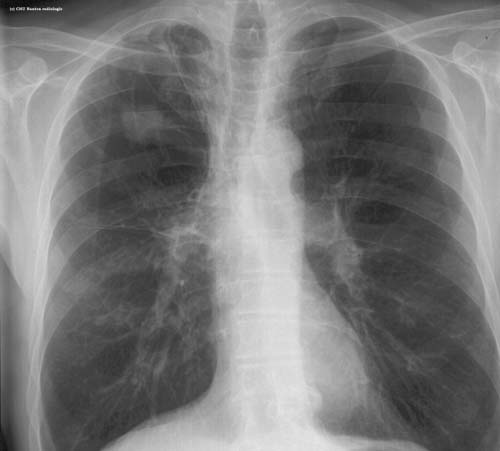

Lésion de type tumeur pulmonaire

légendes